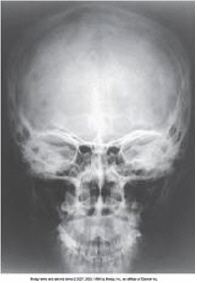

AP axial towne

all of these structures are demonstrated on an AP axial towne projection of the skull except

frontal bone